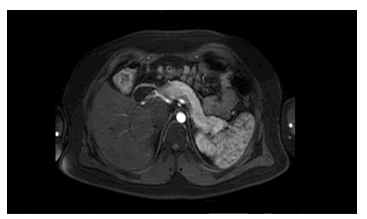

En la resonancia magnética de abdomen, simple y con contraste, no se observaron indicios de lesión intrapancreática (figura 1). Se procedió a practicar una arteriografía abdominal con estimulación intraarterial selectiva pancreática con calcio y con muestreo venoso hepático, para evaluar la concentración de insulina.

Con la sospecha de insulinoma, se indicó una resonancia magnética (RM) con contraste de abdomen, de 1,5 teslas (T). Infortunadamente, la RM en el estudio de insulinoma tiene una tasa de localización correcta promedio de 47,4 %, con una sensibilidad promedio de 53,3 % 27. En este estudio, el páncreas se reportó como completamente normal (figura 1) 28.